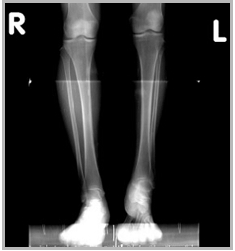

첨족사진

|